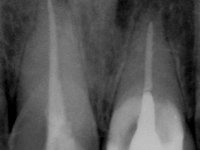

Male patient, 45 years old, smoker, with oesophageal reflux and poor oral hygiene. Teeth 11 and 21 presented an endodontic treatment and tooth 21 was rehabilitated with a Richmond type crown done 12 years ago. Tooth 11 presented an extensive restoration in composite resin in the buccal surface bonded exclusively to dentin. The palatal surface presented acid erosion and an extensive reconstruction in the endodontic access. The clinical crown was 4,5mm height and the root had 11mm.

• Do not prepare the root canal to prevent its weakness.